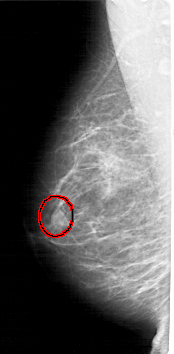

A_1982_1.RIGHT_CC

RIGHT_CC LINES 4756 PIXELS_PER_LINE 2206 BITS_PER_PIXEL 12 RESOLUTION 43.5 NON_OVERLAY

FILE: A_1982_1.LEFT_CC.OVERLAY

TOTAL_ABNORMALITIES 1

ABNORMALITY 1

LESION_TYPE MASS SHAPE OVAL MARGINS ILL_DEFINED

ASSESSMENT 4

SUBTLETY 3

PATHOLOGY BENIGN

TOTAL_OUTLINES 1

BOUNDARY